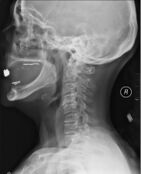

X-rays (left) are more available, but can miss details like herniated disks that MRIs can show (right).[88]

A radiographic evaluation using an X-ray, CT scan, or MRI can determine if there is damage to the spinal column and where it is located.[9] X-rays are commonly available[88] and can detect instability or misalignment of the spinal column, but do not give very detailed images and can miss injuries to the spinal cord or displacement of ligaments or disks that do not have accompanying spinal column damage.[9] Thus when X-ray findings are normal but SCI is still suspected due to pain or SCI symptoms, CT or MRI scans are used.[88] CT gives greater detail than X-rays, but exposes the patient to more radiation,[90] and it still does not give images of the spinal cord or ligaments; MRI shows body structures in the greatest detail.[9] Thus it is the standard for anyone who has neurological deficits found in SCI or is thought to have an unstable spinal column injury.[91]